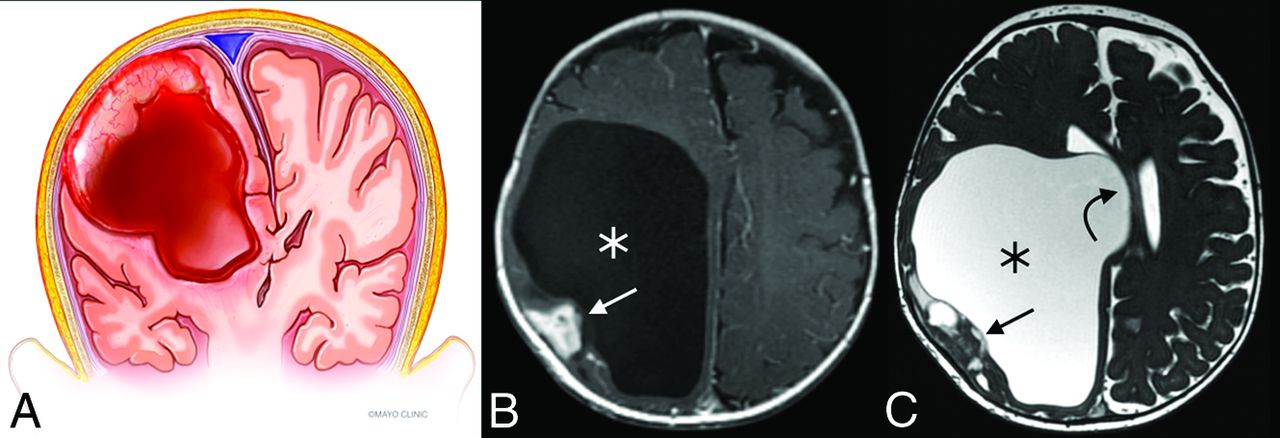

Multiple characteristic features make DITs recognizable entities on imaging, though the differentiation between DIG and DIA requires histologic analysis. The tumors are invariably supratentorial, contain solid and cystic components, and are often of substantial size.5,9 Involvement of multiple lobes is common, with a predilection for the frontoparietal regions.16,17 The solid component tends to be located peripherally, along the dural side of the tumor, and is usually T2 iso-/hypointense to gray matter with avid enhancement (Fig 4).9,10 Typically, the dura or leptomeninges adjacent to the solid nodule or both demonstrate enhancement.9 Extremely rare purely solid and nonenhancing DIGs have been reported, as have DIGs in a suprasellar location.18

Illustration (A) and example (B and C) of a DIT with typical features. The tumors are exclusively supratentorial and voluminous and are made up of both cystic (asterisks) components and a peripheral mural nodule (straight arrows). Significant associated mass effect and midline shift (curved arrow) are often present. Illustration (A), Used with permission of Mayo Foundation for Medical Education and Research. All rights reserved.